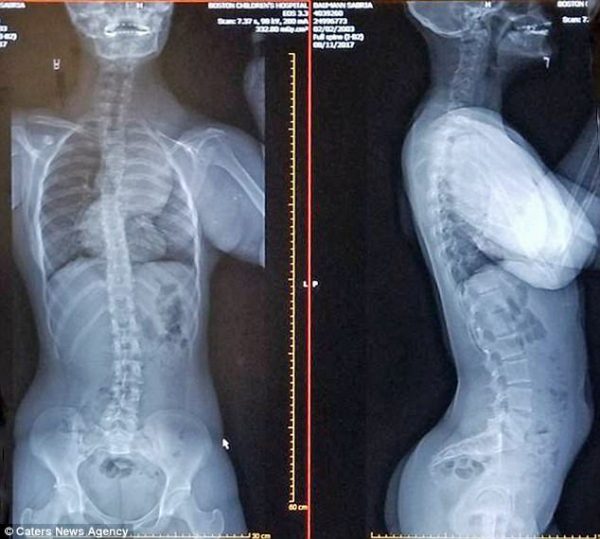

Америкийн Техас мужийн Бриа Бауманн охин “CLOVES syndrome”-той төрсөн байна. Энэ нь нэн ховор төрлийн өвчин бөгөөд дэлхий дээр ийм 200 хүн байдаг аж. Биеийн хаана ч хавдар үүсч болдог аюултай.

Өнөөдөр хүртэл түүнийг амьд байлгахын тулд чадварлаг эмч нар 38 хагалгаа хийсэн. 14 сартай байхад нь хийсэн хагалгааны дараа маш хүнд байдалд байсан бөгөөд эх нь дэлхийн алдартай эмч нарыг хайж эхэлсэн аж. Тэднийг олсны дараа охиныг нь амьд байлгах итгэл найдварыг өгөөд байгаагаа илэрхийлжээ.

Биеийн бүтэц нь хэвийн бус харагдах ч гэлээ тэр өдөр бүр дасгал сургуулилтаа хийж, завгүй байдаг.